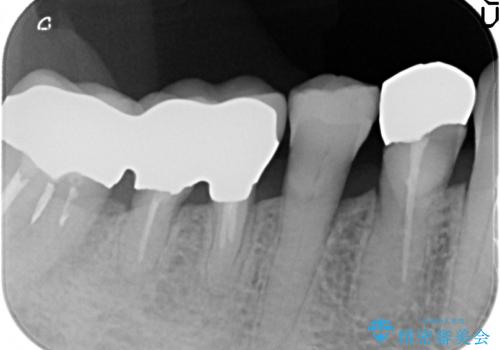

歯ぐきから血が出る、歯ぐきが腫れている 80代女性

- 歯ぐきからの出血と腫れを主訴に来院された患者様です。

プラークコントロールが非常に悪く、全顎的な歯周病に罹患していました。

「抜歯したくない、インプラントは嫌」という患者様のご希望とご年齢を考慮し、可及的な骨外科処置や根分割術によりできるだけ今ある歯を残す治療方針をたてました。

保存不可能な左上の奥歯2本(左上67)は抜去し、ノンクラスプデンチャーをいれることにしました。

長期的な予後は保証できないことをご了承頂いた上で治療を行いました。

ご希望により、積極的な再根管治療は行いませんでした。